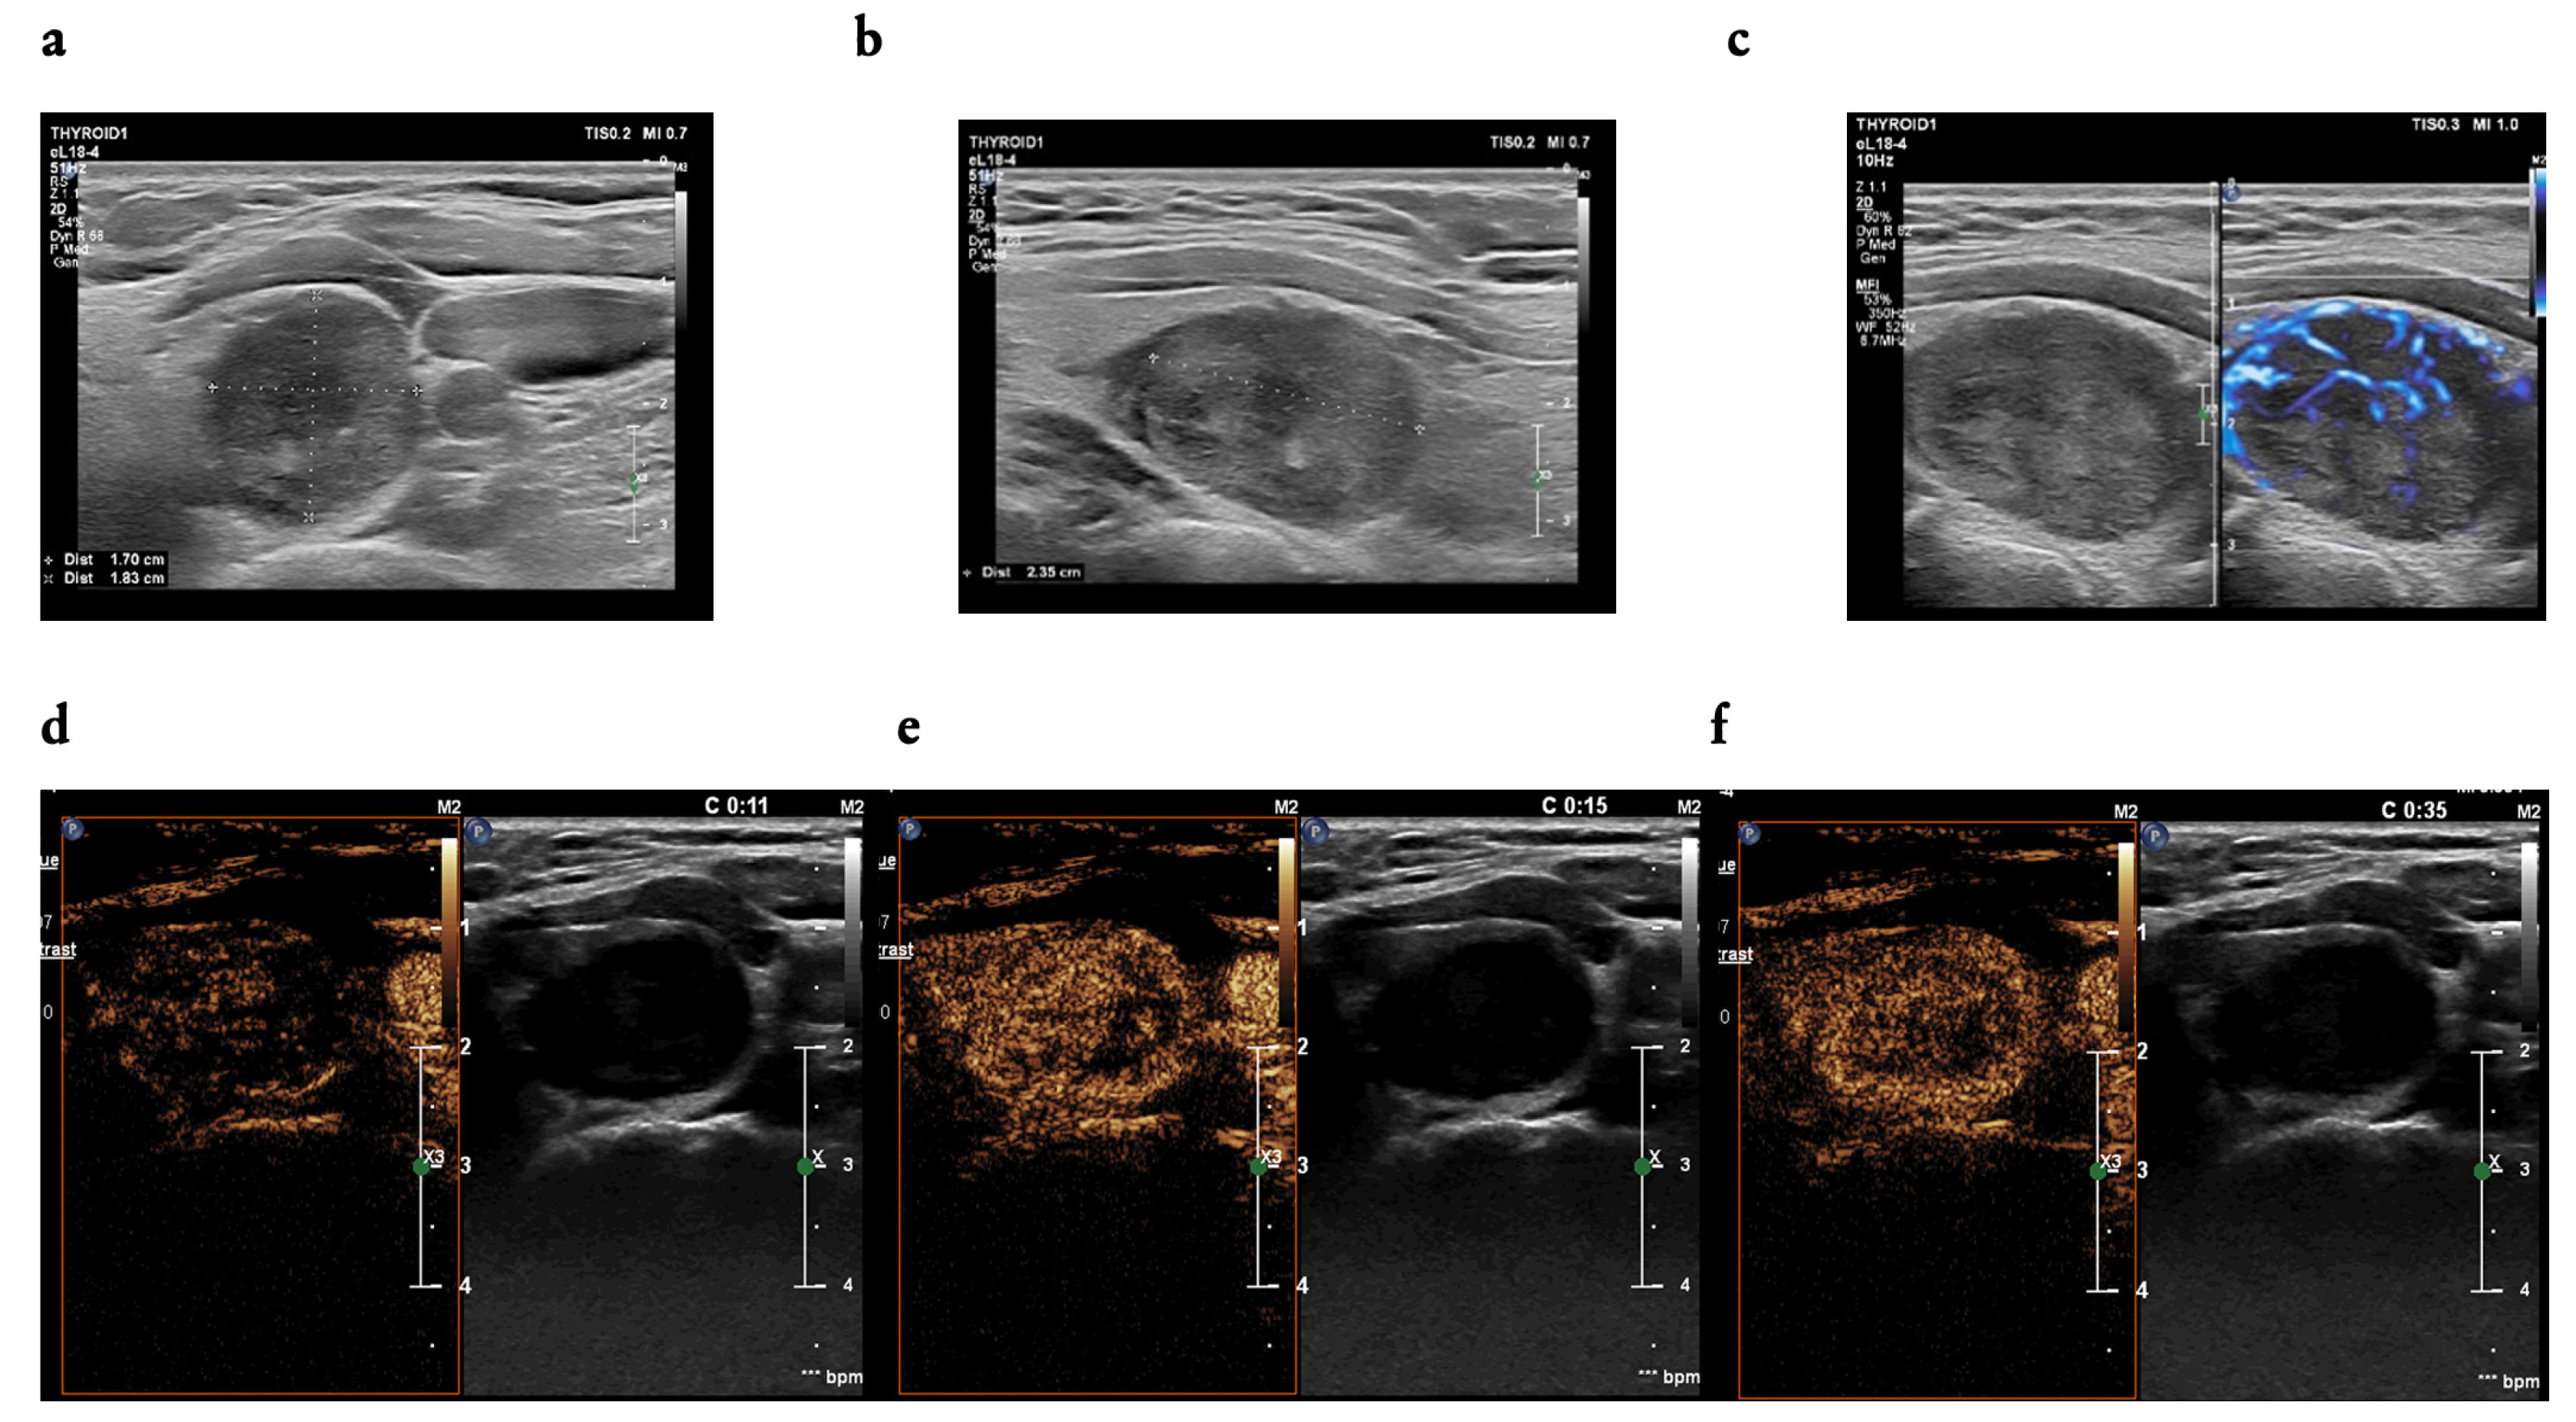

3.2. B-Mode Findings

3.3. CEUS Findings

4.5. The Utility of CEUS Patterns Assessed in the Study in Line with the Literature Review—Benign Nodules